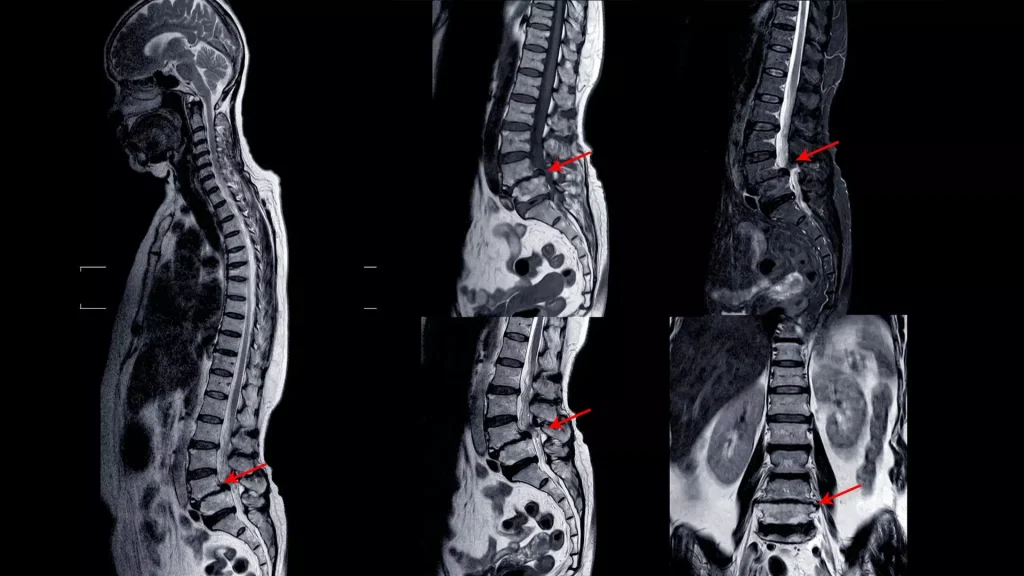

Mielopatía ¿Qué es la mielopatía? La mielopatía es una alteración de la médula espinal provocada por su compresión o daño